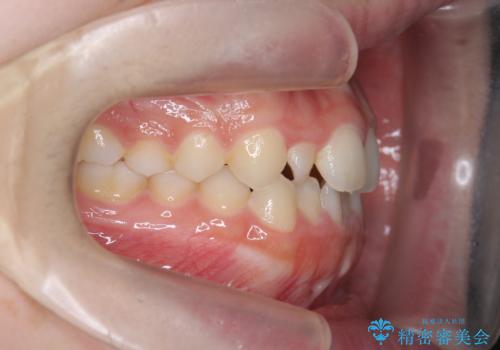

前歯のガタつき・ねじれを治すマウスピース矯正

- 前歯のねじれ、ガタつきを改善し綺麗な歯並びにしたいと希望され来院されました。

マウスピース矯正インビザラインによる矯正治療を計画しますが、マウスピース矯正で治りにくい歯のねじれを事前にワイヤー矯正でしっかりとなおしておくことで矯正治療期間の短縮できるような治療計画を立てます。

マウスピース矯正を始める前にワイヤー部分矯正を行ったことで改善のしにくい歯のねじれをしっかりと治すことができました。